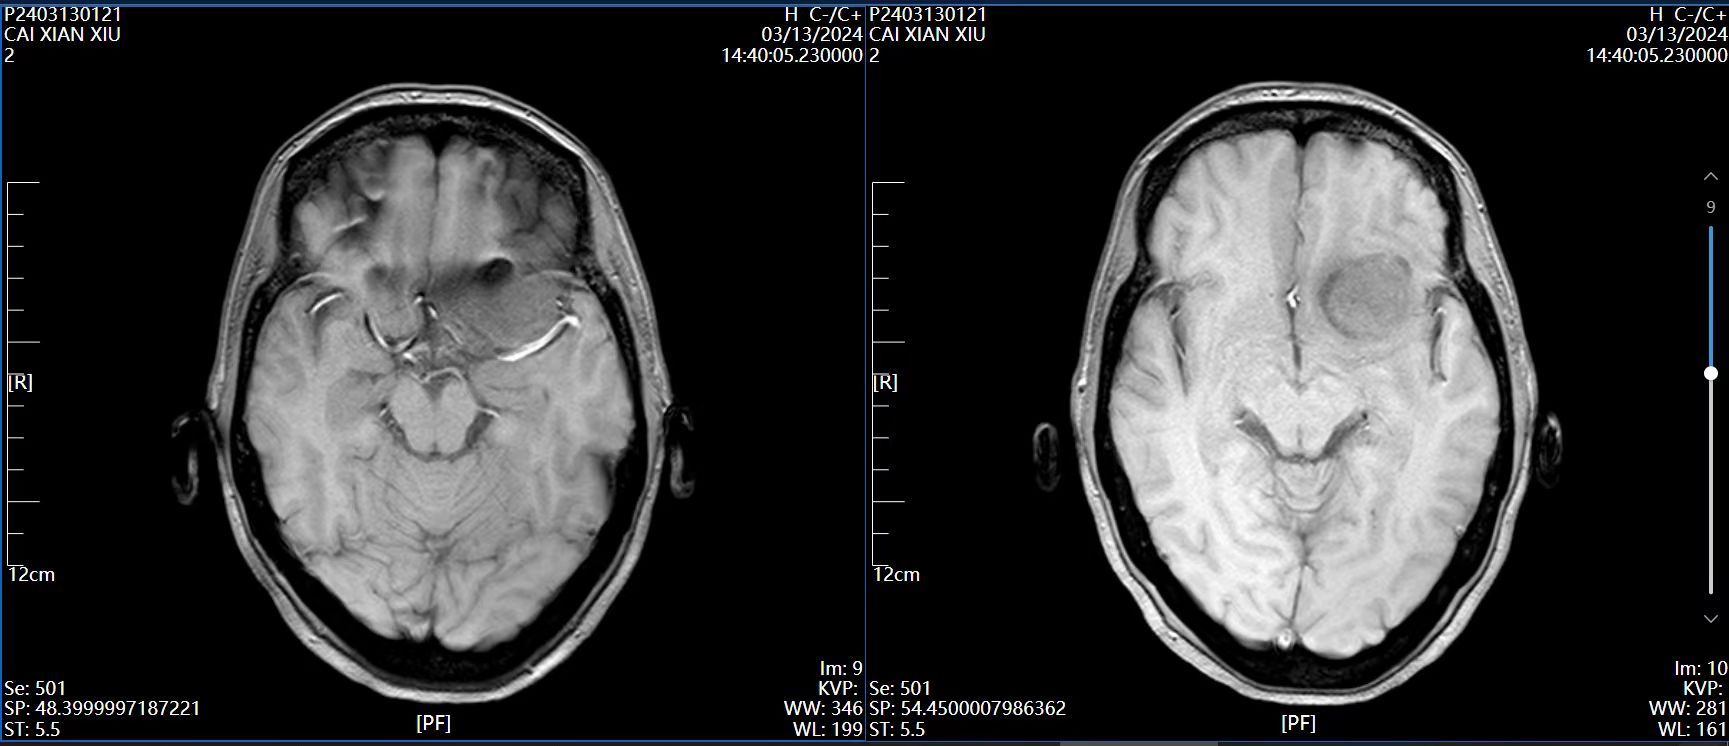

4、辅助检查:头颅磁共振检查提示:左侧前床突占位,约2.8×2.4×2.0cm大小,T1呈等低信号,T2呈等高信号,增强病灶明显强化,宽基底与前颅窝底、前床突相连,看见脑膜尾征。

磁共振 T1